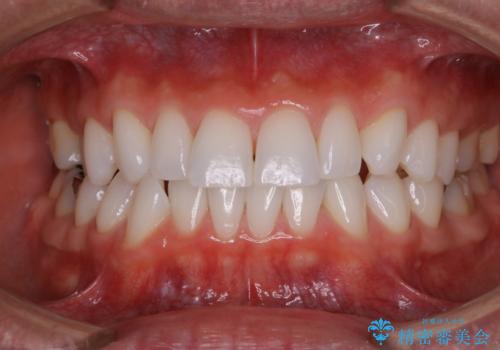

全体的な治療の開始前に着色取り